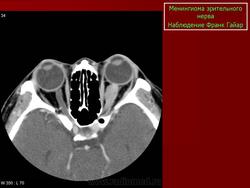

КТ-семиотика

На КТ срезах без контрастного усиления менингиома зрительного нерва выглядит изоденсной. Типично наличие линейных или точечных обызвествлений. Симптом «трамвайных рельс» отражает накопление КВ по сторонам гиподенсного зрительного нерва или наличие обызвествлений в структуре опухоли. Как правило, наиболее дистальная часть зрительного нерва, в месте его вхождения в глазное яблоко, не содержит обызвествлений.

При исследовании необходимо определить расположение бляшковидной менингиомы относительно бугорка турецкого седла и пластинки клиновидной кости, так как данный тип опухоли может распространяться интракраниально через канал зрительного нерва. КТ не позволяет адекватно визуализировать интракраниальное распространение опухоли, которое может привести к развитию двусторонней слепоты.